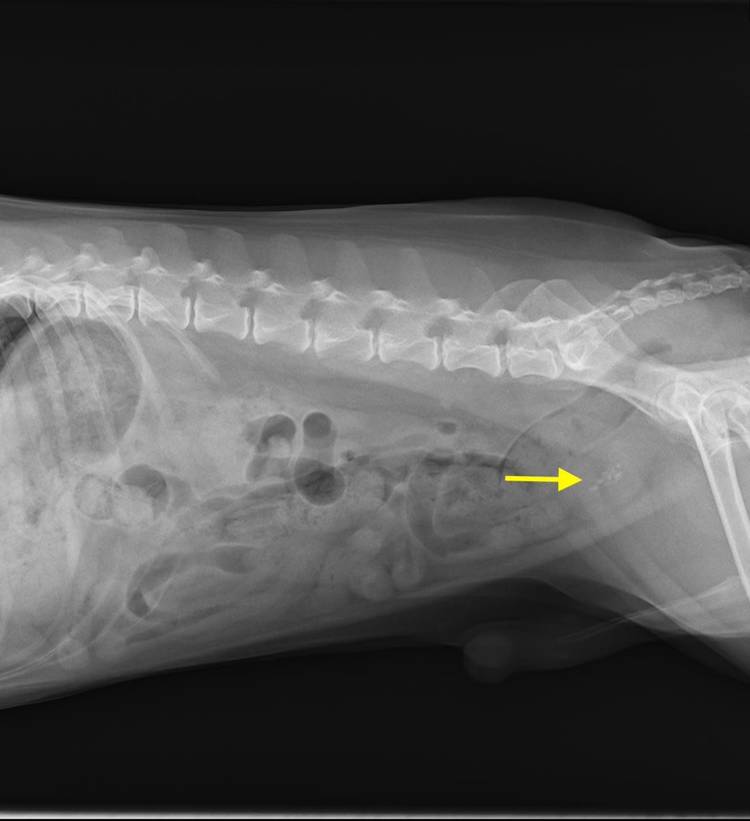

【今年も秋の健康診断キャンペーンを実施します❗️】 暑い日が続いておりますが、9月になると徐々に秋が近付いてきますね🍁 秋といえば毎年恒例の健康診断キャンペーンを、今年も9/1~11/30の期間で実施します(moon big smile) 秋の健診パックにはレントゲンやエコーの画像検査が含まれており、春と秋の健診を実施していただくことでペットの健康管理をしっかりと行うことができます。 健診の...